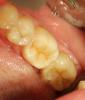

METT Опубликовано 13 апреля, 2013 Автор Поделиться Опубликовано 13 апреля, 2013 37 точево,вкладку еще не фотал Ссылка на комментарий

METT Опубликовано 13 апреля, 2013 Автор Поделиться Опубликовано 13 апреля, 2013 26 точево Ссылка на комментарий